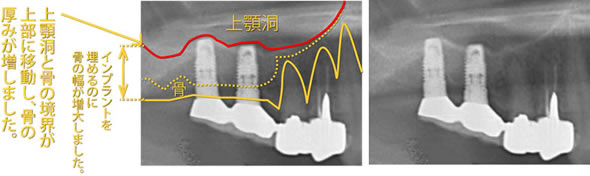

上顎洞挙上術(サイナスリフト)

上顎の大臼歯部では、上顎洞(副鼻腔の一つ)が近接しているため、骨の厚みが不足していることが多いです。特に抜歯後は骨吸収が進み、インプラント埋入に十分な骨量が確保できないことがあります。こうした場合、上顎洞底部に骨補填材を移植し、骨の再生・増殖を促す上顎洞挙上術を行うことで、インプラント治療を可能にします。

上顎の骨が薄く、上顎洞(副鼻腔) までの距離が4mmしかないので このままではインプラントを埋め込むことができません。